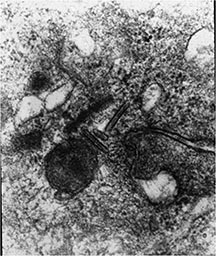

- Langerhans cell is diagnostic and clonal proliferation

- Nuclei show prominent nuclear groove (coffee-bean)

- Also composed of eosinophils and other inflammatory cells (non diagnostic component)

- Ratio of inflammatory cells to Langerhans cells varies

- Mitotic activity low

- Eosinophils dominate some areas forming diffuse sheets, excluding Langerhans cells

- Birbeck Granules: Electron Microscopy demonstrates granules that often take the form of a tennis raquet and form from complex invaginations of the cell membrane